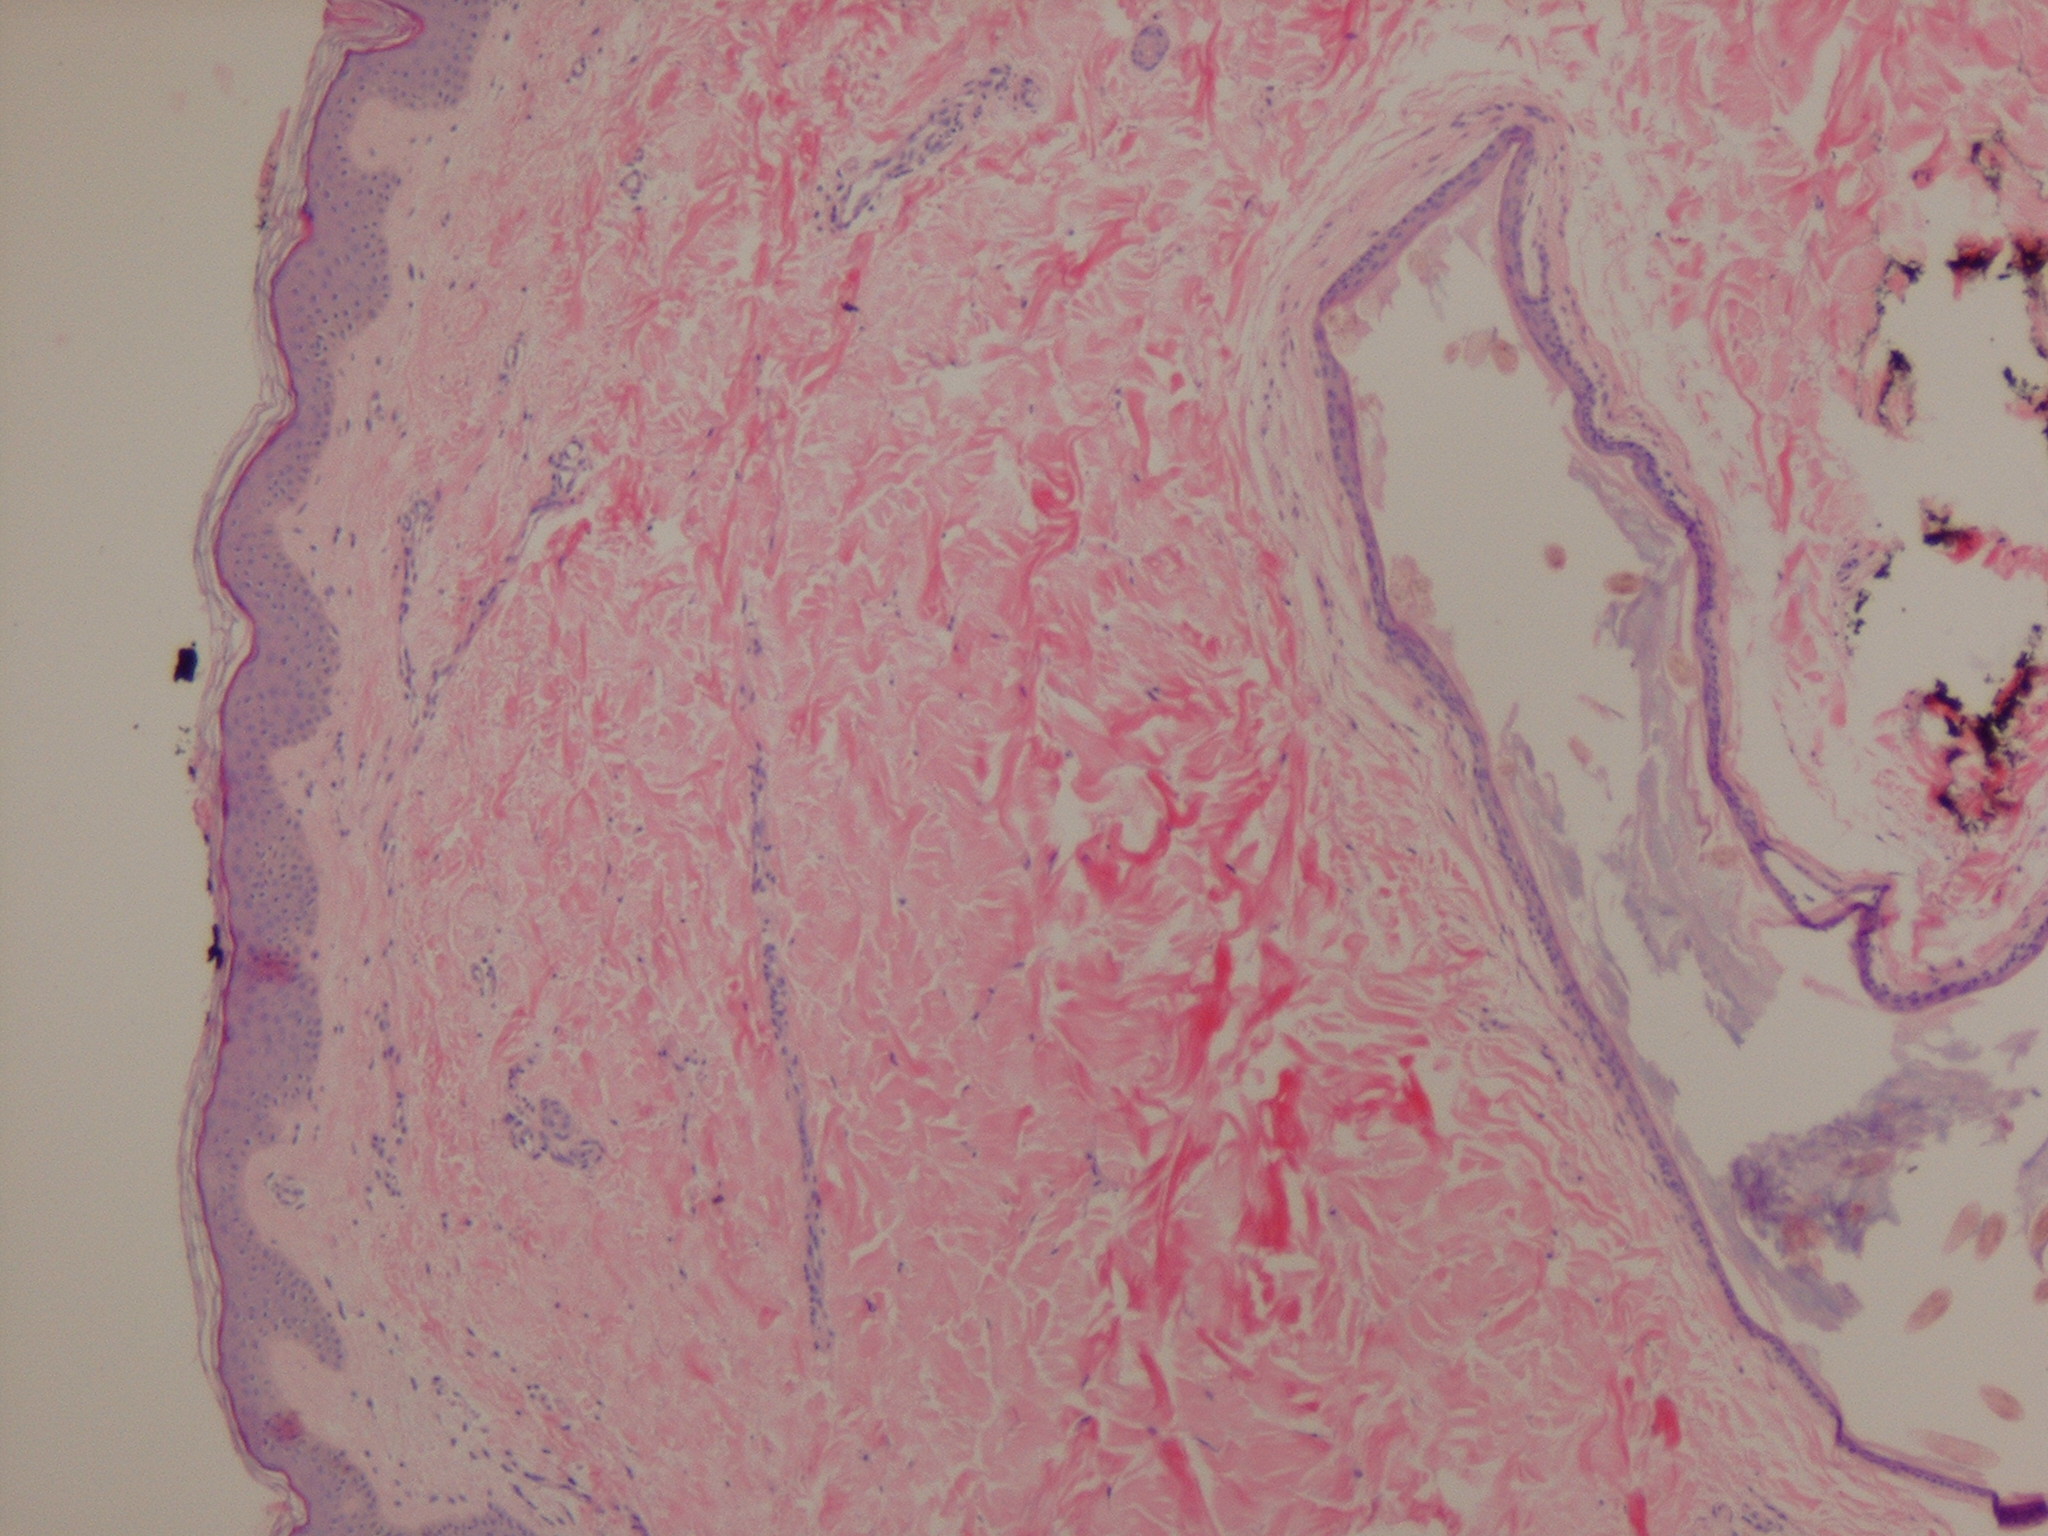

Vellus hair cysts = كيسات الشعر الزغبي